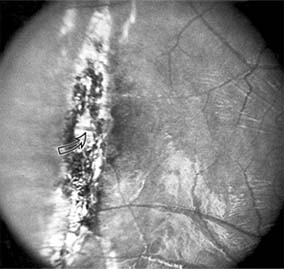

Figure 10-13

Figure 10-13: Traumatic choroidal rupture resulting in pigmented scar. A choroidal vessel (arrow) is visible through the scar.